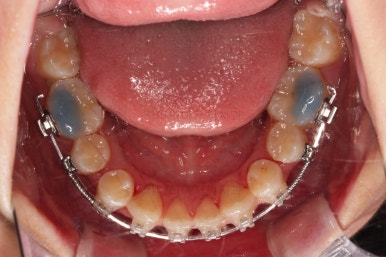

윗니는 틈을 점점 줄여가고요.

아랫니는 중간에 오히려 틈이 생기고 있죠?

이런 효과로 위아래 앞니는 급속도로 가까워지게 됩니다.

아랫니는 이후에 어금니를 앞으로 당겨오면서 빈공간을 줄여 나갑니다.

교합이 점점 맞아가네요.

윗니 뽑은 자리도 거의 다 줄었습니다.